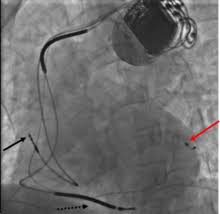

Marcapasso especial se mostra ineficaz em quase metade dos implantes

Um tipo especial de marcapasso é incapaz de ajudar quase metade dos doentes cardíacos que o adquirem.

O dispositivo implantável chamado marcapasso biventricular foi projetado para corrigir irregularidades nas contrações dos ventrículos, fato que às vezes ocorre nos pacientes com insuficiência cardíaca. O marcapasso é usado normalmente nos pacientes em que a medicação não se mostrou eficaz. Mais de 50 mil são implantados todos os anos.